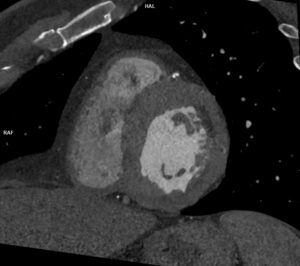

Video 2: reconstrucție axială din achiziție angioCT cu sincronizare ECG

Discuţie caz nr 54 : la nivelul septului interatrial în mod normal există foramen ovale care, dacă este patent, poate permite trecerea contrastului din atriul stâng în atriul drept în cantitate mică. Punerea în evidență la examinarea CT a circulației substanței de contrast dinspre atriul stâng spre atriul drept sugerează necesitatea completării cu ecografie transesofagiană pentru interogarea septului interatrial dar și evaluarea cavităților cardiace drepte precum si interogarea existenței unui eventual drenaj venos pulmonar aberant. Măsurătorile efectuate sunt utile în planificarea închiderii DSA.